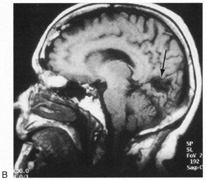

Fig. 9. Macular-sparing striate hemianopia. A 49-year-old woman with headache and difficulty seeing to the left for 1 week. A. Fields show left hemianopia that spares a small zone around the central fixation spot. B. Magnetic resonance imaging shows infarct of right striate cortex, with sparing of occipital pole. (From Rosen ES, Eustace P, Thompson HS, Cumming WJK [eds]: Neuro-Ophthalmology. London: Mosby, 1998.)

Partial lesions of the striate cortex are frequent. With posterior cerebral infarcts, a macula-sparing hemianopia occurs in patients with adequate collateral circulation of the macula region (occipital pole) from the middle cerebral artery (Fig. 9).35 Previously, macula-sparing was thought to result from bilateral representation of a small stripe flanking the vertical meridian, which expanded to as much as 3° at the fovea.41 However, studies of monkey V1 do not find bilateral representation of the hemimaculae,42 and computed tomography (CT) and magnetic resonance imaging (MRI) studies in humans with hemianopia document the correlation of macular sparing with sparing of the occipital pole.43,44 Also, careful perimetry of hemianopes with the scanning laser ophthalmoscope shows that, although there is a slight overlap from the seeing field into the blind field along the meridian, macular sparing of 2° to 5° is only present in some patients.45,46 Therefore sparing more likely reflects the extent of occipital pathology than retinal anatomy. Macula-sparing has some localizing value, because it is seen mainly with lesions of striate cortex.